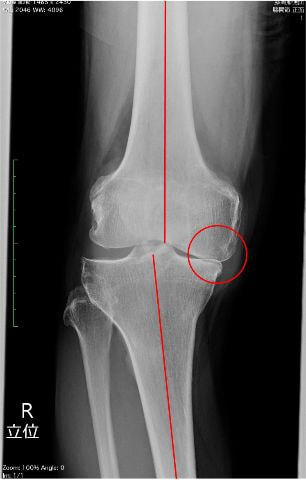

外来通院での運動療法と関節注射を継続して行っていましたが、レントゲンでは膝関節内側の関節軟骨がすり減って、上下の骨が衝突しており、痛みも強いことから手術適応となりました。(左写真)